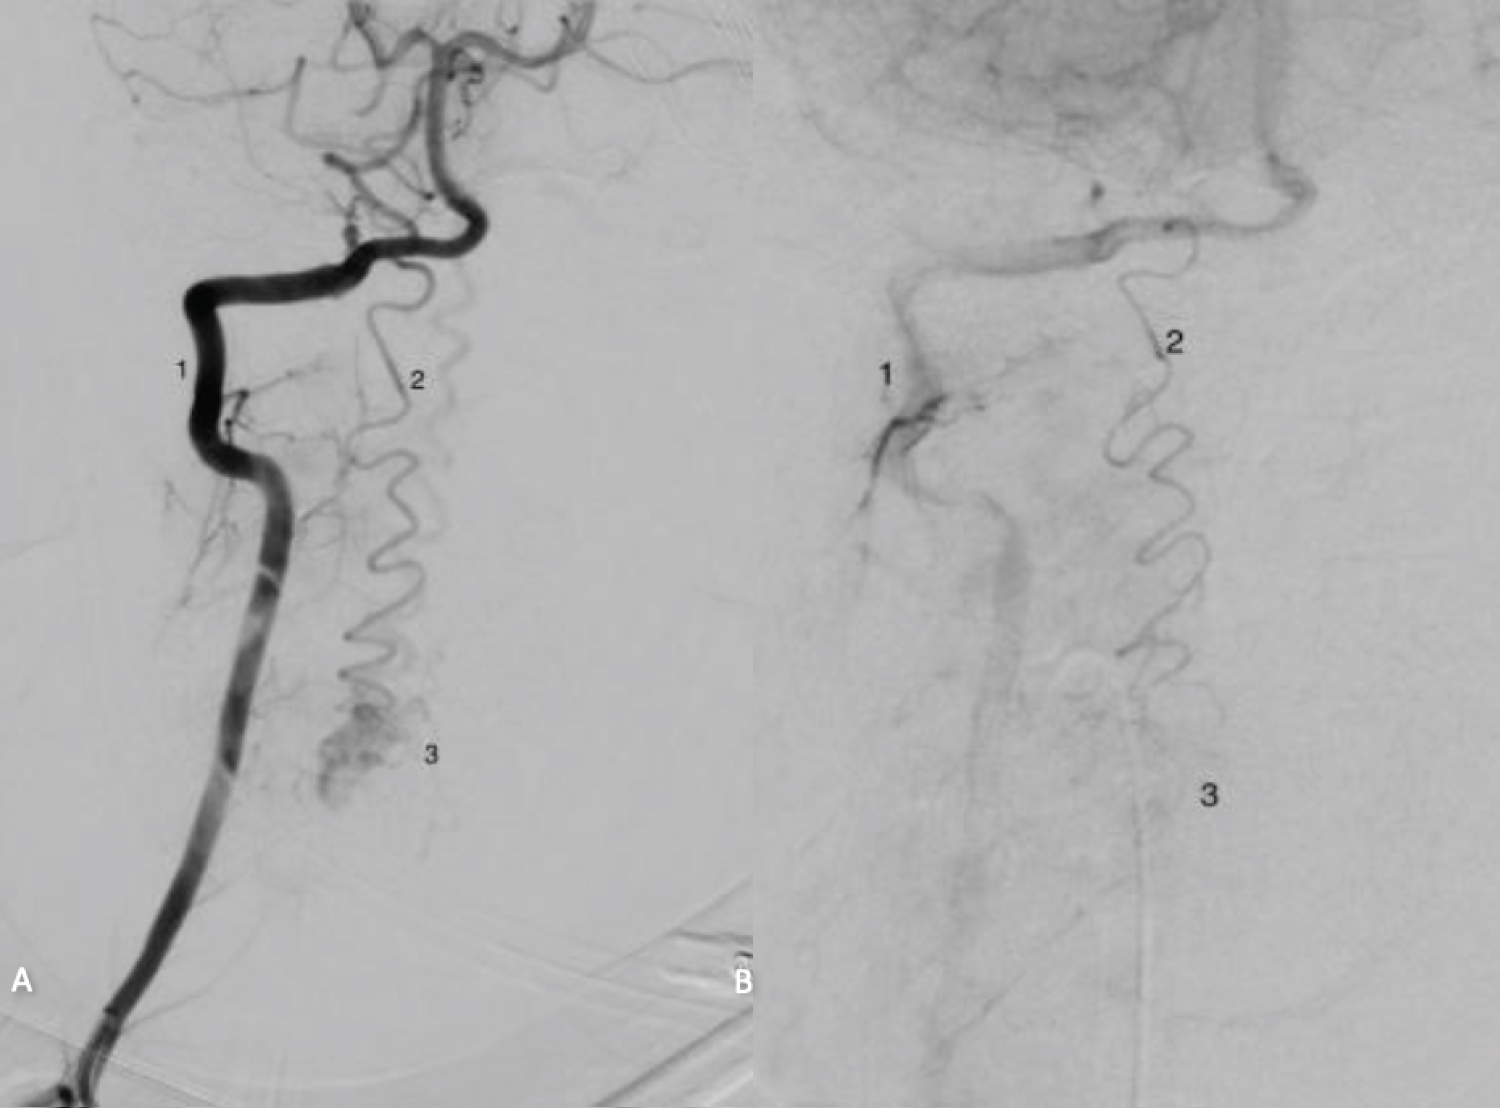

Digital subtraction angiography (DSA) was performed which confirmed the presence of a complex arteriovenous malformation arising from the V3 segment of the right posterior spinal artery and a caudal inflow originating from the right thyrocervical trunk, measuring 7 mm horizontally and 15 mm vertically. The main nidus of the AVM was located at the C5 level. While the primary venous drainage of the AVM occurred through the superior bulb of the internal jugular vein, a minor portion drained via epidural veins (Figure 1).

Figure 1: Preoperative MRI scan of the cervical and thoracic spine. (A) T2-weighted sagittal image shows hyper-intense cord signal as well as cord edema on level C4-C6 (white arrow); (B) Corresponding T1 weighted sagittal image; (C) DSA showing the central nidus of the AVM (3) with feeding vessel (2) originating from V3 segment of the right vertebral artery (1). View Figure 1

Cannulations of the feeding vessels were performed using a flow-directed microcatheter (Synchro-10, Marathon) and liquid embolic agent (20% Magic glue) was injected closed to the nidus. Complete obliteration was achieved after second intervention (Figure 2).

Figure 2: Intra-procedural DSA. (A) Before treatment; (B) Post-glue embolisation shows the obliteration of AVM (3). View Figure 2